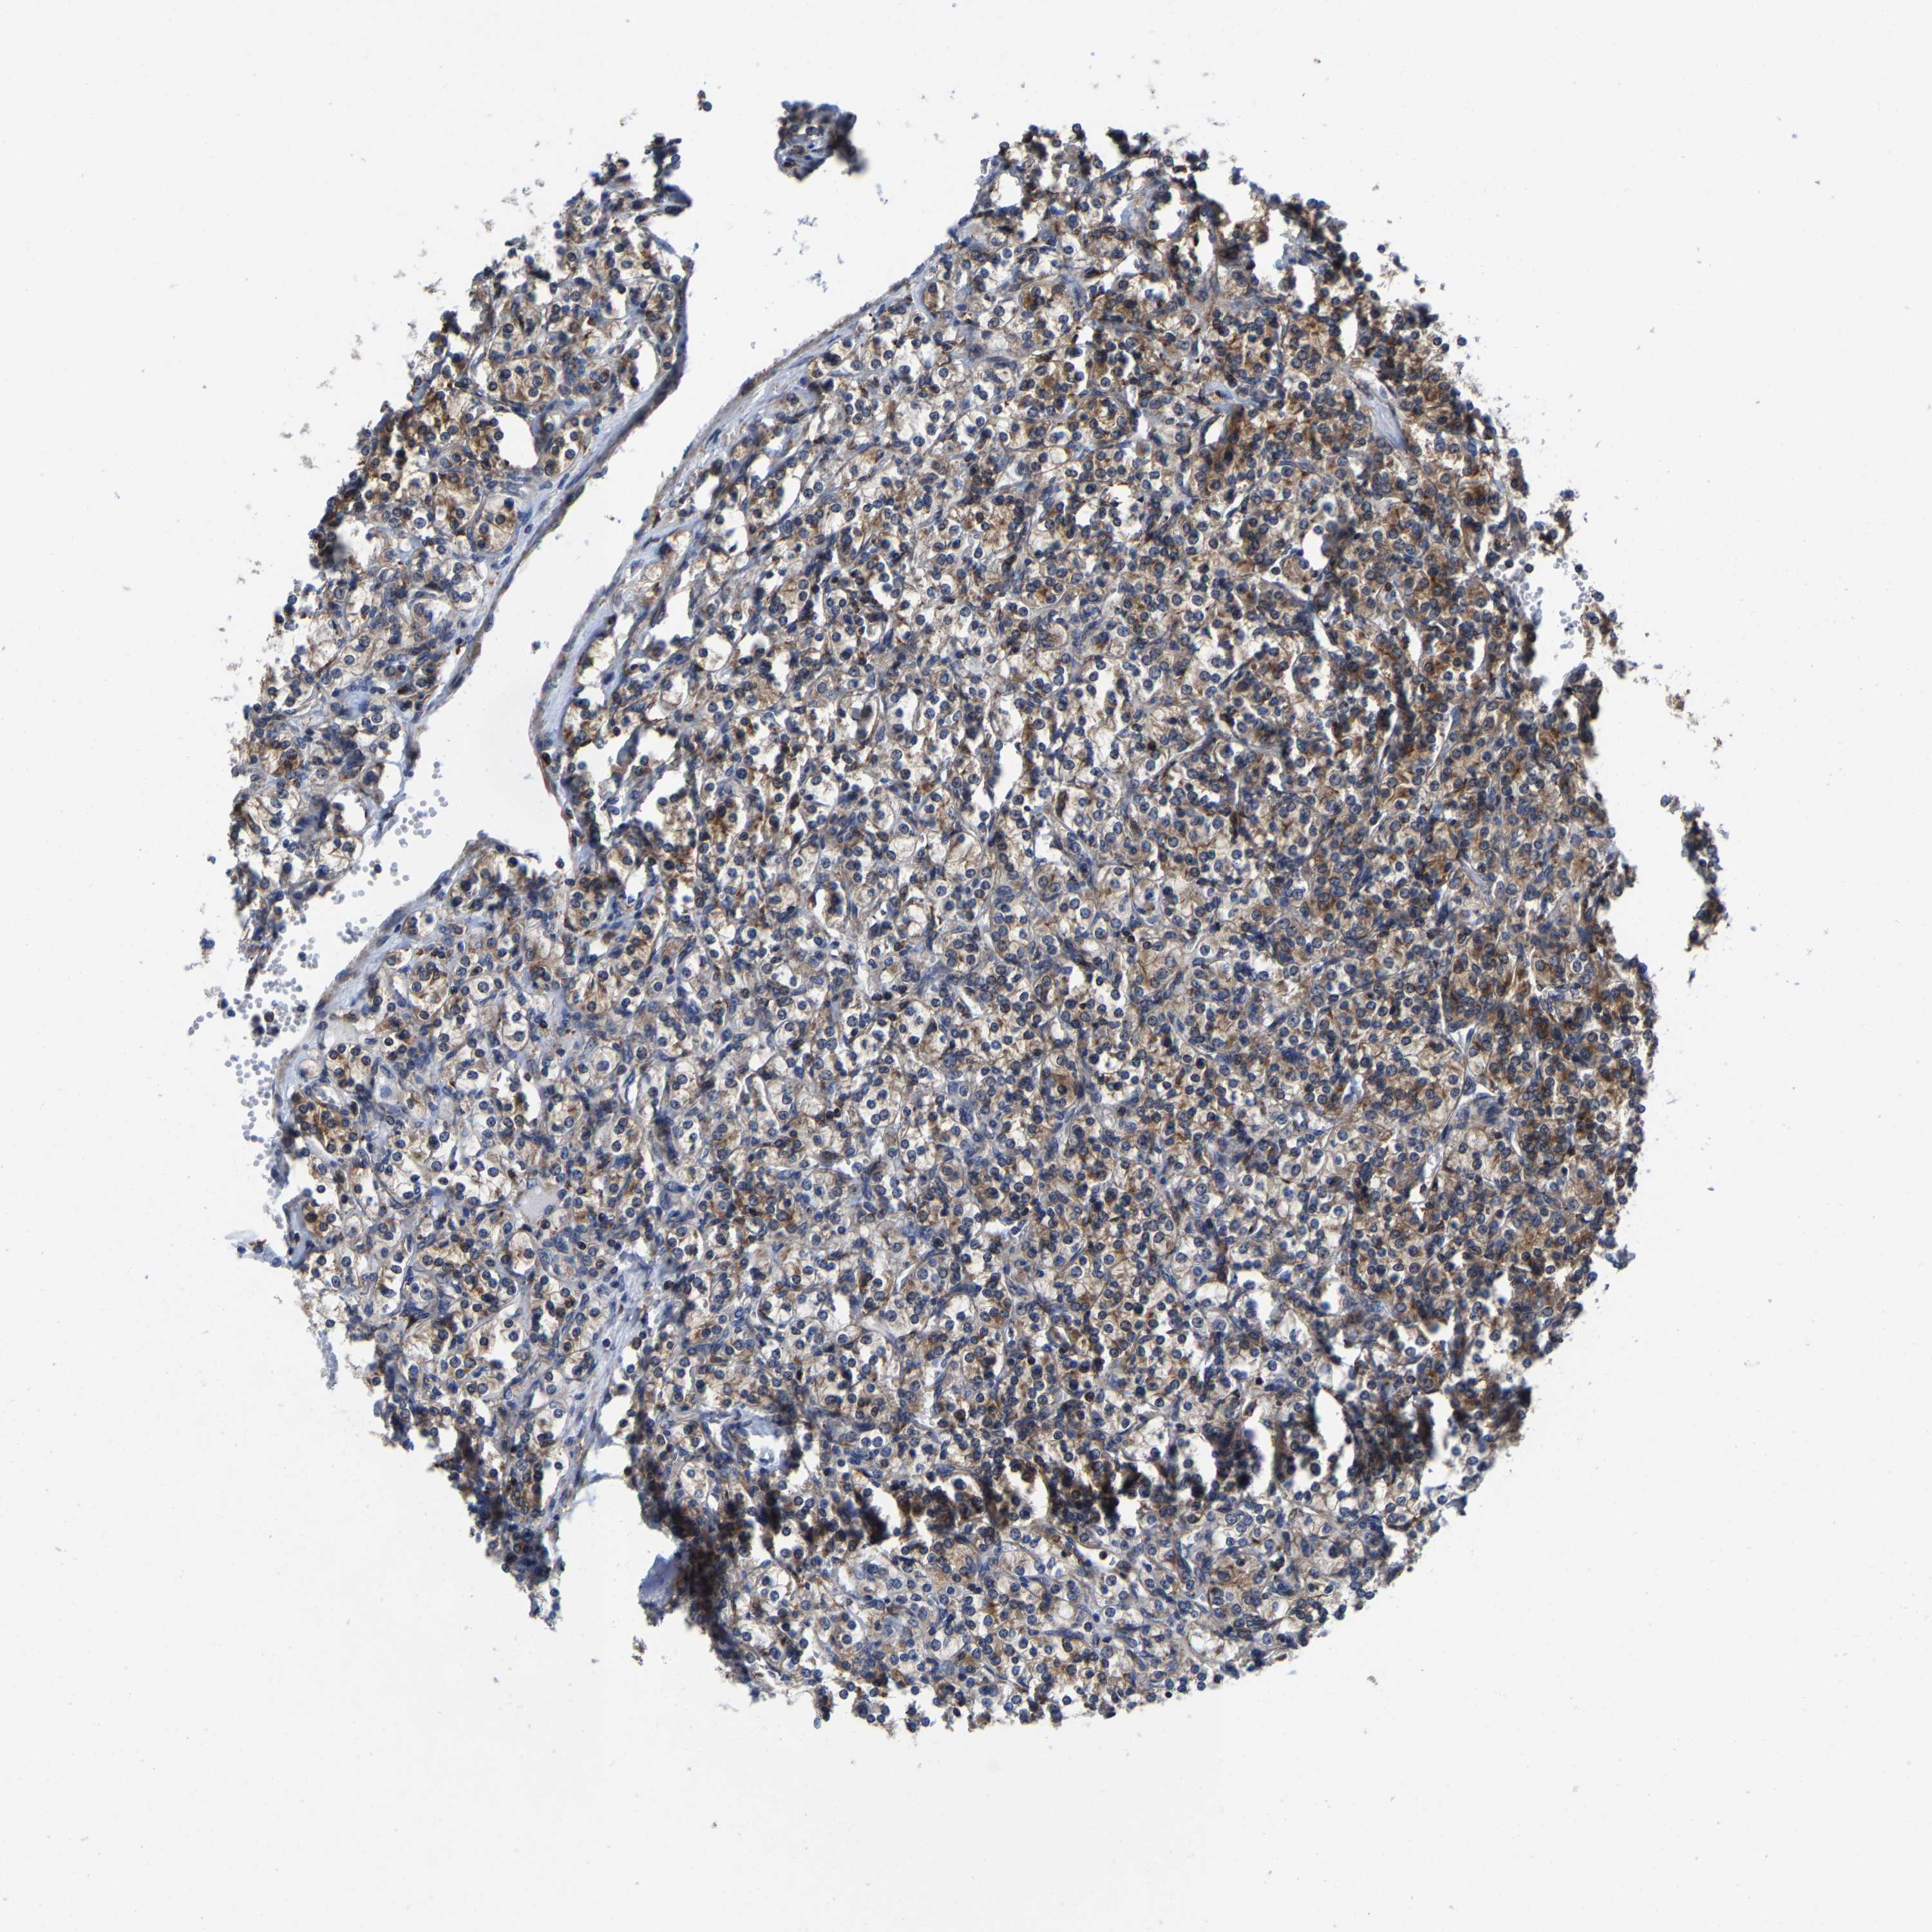

KIDNEY RENAL PAPILLARY CELL CARCINOMA (TCGA) - Interactive survival scatter ploti

The Survival Scatter plot shows the clinical status (i.e. dead or alive) for all individuals in the patient cohort, based on the same data that underlies the corresponding Kaplan-Meier plots. Patients that are alive at last time for follow-up are shown in blue and patients who have died during the study are shown in red.

The x-axis shows the expression levels (FPKM) of the investigated gene in the tumor tissue at the time of diagnosis. The y-axis shows the follow-up time after diagnosis (years). Both axes are complimented with kernel density curves demonstrating the data density over the axes. The top density plot shows the expression levels (FPKM) distribution among dead (red) and alive patients (blue). The right density plot shows the data density of the survived years of dead patients with high and low expression levels respectively, stratified using the cutoff indicated by the vertical dashed line through the Survival Scatter plot. This cutoff is automatically defined based on the FPKM cutoff that minimizes the p-score. The cutoff can be changed by dragging the vertical line or by entering a cutoff value in the square labeled "Current cut-off".

Under the Survival Scatter plot the p-score landscape (black curve; left axis) is shown together with dead median separation (red curve; right axis). Dead median separation is the difference in median mRNA expression between patients who have died with high and low expression, respectively. It is calculated as follows: median FPKM expression of dead patients with high expression - median FPKM expression of dead patients with low expression. This is intended to aid the user in visually exploring custom cutoffs and the associated p-scores and dead median separation.

Individual patient data is displayed and can be filtered by clicking on one or more of the category buttons on the top of the page. Categories describing expression level and patient information include: high, low, alive, dead, female, male and tumor stages. The scale of the x-axis can be toggled between linear and log-scale by clicking on the "x log" button. Mouse-over function shows TCGA ID, patient information and mRNA expression (FPKM) for each patient.

& Survival analysisi

Kaplan-Meier plots summarize results from analysis of correlation between mRNA expression level and patient survival. Patients were divided based on level of expression into one of the two groups "low" (under cut off) or "high" (over cut off). X-axis shows time for survival (years) and y-axis shows the probability of survival, where 1.0 corresponds to 100 percent.

PFKFB3 is not prognostic in Kidney Renal Papillary Cell Carcinoma (TCGA)